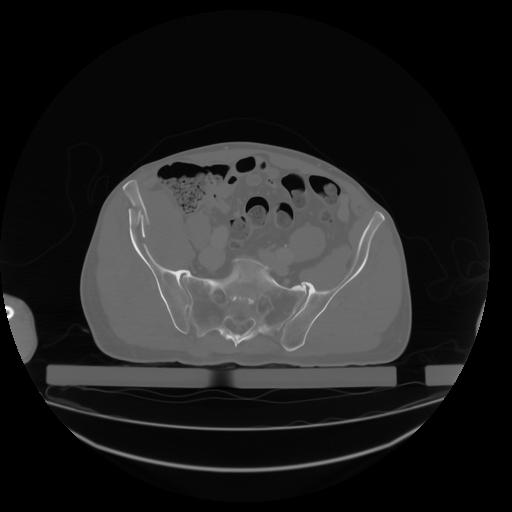

27 CUERPO,CE,Axial,3.0,CUERPO,,